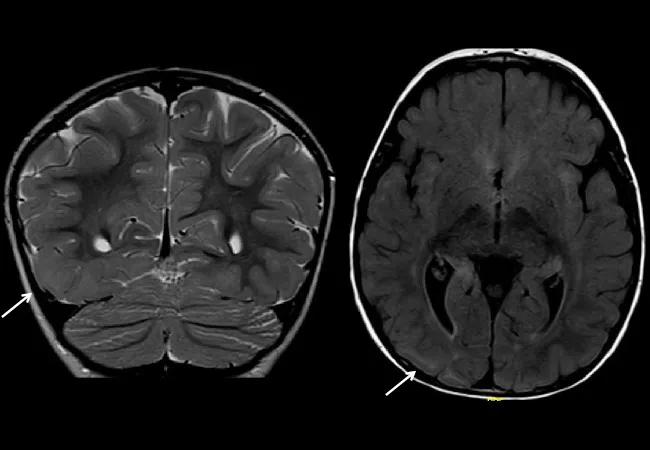

To confirm the presence of a focal cortical malformation beyond all doubt, a third MRI was performed at 22 months. This time, the findings were incontrovertible: With more advanced brain maturation and myelination, the extensive right temporoparietal occipital malformation was clearly visible.

In contrast with EEG, the MRI in infants may provide greater localizing information over time as myelination progresses and the gray-white matter junction becomes increasingly distinct. As illustrated by reports from Sankar et al (Am J Neuroradiol. 1995;16:1265-1272) and Kang et al (Brain Dev. 2013;35:816-820), some focal malformations of cortical development may only become clearly apparent with serial imaging over time.

MRI sequencing may also play a role. In infants, T2 sequences are most useful for detecting focal cortical dysplasia, while FLAIR sequences can be highly misleading. One of the concerns about this girl’s first MRI was that it included only limited T2-weighted sequences.